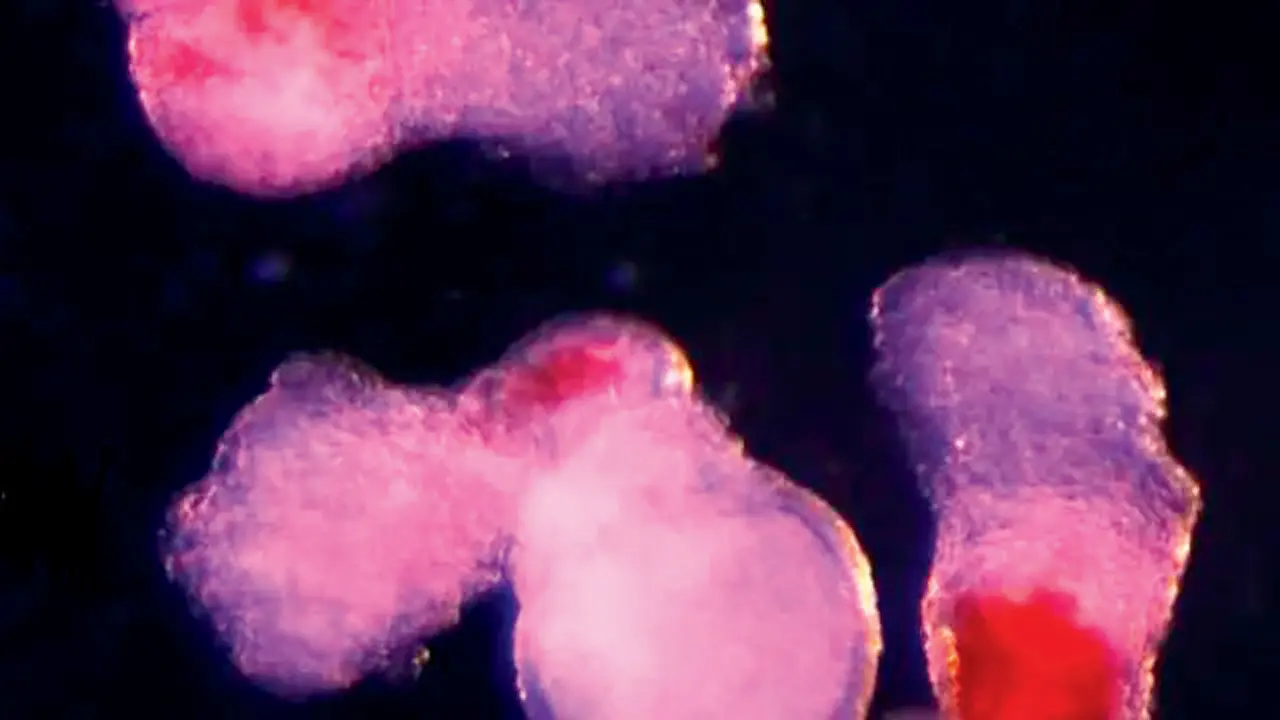

Scientists at the University of Cambridge have developed hematoids, lab-grown embryo-like structures that produce human blood stem cells. This breakthrough could help study blood disorders like leukaemia and generate stem cells for long-term transplants